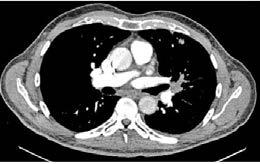

Mujer de 73 años con antecedentes de hipertensión arterial, trombopenia en contexto de lupus eritematoso sistémico, episodio de hipotiroidismo inducido por amiodarona y fibrilación auricular (FA) en estrategia de control de frecuencia cardiaca, anticoagulada con antivitamina K. Como fundamental antecedente cardiológicos destaca una valvulopatía reumática con afectación mitral, que inicialmente se reparó en 1997 mediante abordaje transapical (dejando como secuela aneurisma apical) y se recambió en 2007 por prótesis mecánica. Posteriormente, fue diagnosticada de doble lesión aórtica reumática con estenosis severa e insuficiencia ligera, con fracción de eyección preservada, pero insuficiencia tricuspídea severa e hipertensión pulmonar de predominio poscapilar. Ingresó programada para implante percutáneo de válvula aórtica (TAVI) vía transfemoral, con los principales condicionantes de bloqueo de rama derecha y altura límite de tronco coronario izquierdo (TCI), por lo que se administró clopidogrel 600 mg previamente al procedimiento.

Previo implante de marcapasos temporal yugular derecho se llevó a cabo el procedimiento. Durante la liberación de prótesis mediante inflado del balón, tuvo lugar la embolización supra-anular de la misma, dejando por un lado una insuficiencia aórtica severa y por otro lado ocluyendo parcialmente ambos troncos coronarios. Empleando doble acceso radial se enganchó la prótesis mediante un lazo y se desplazó hacia aorta ascendente, dejando hueco para la colocación de una segunda prótesis en situación correcta y evitando la oclusión de los ostium coronarios y troncos supra-aórticos. En ausencia de bloqueo auriculoventricular se retiró el marcapasos temporal, se evidenció un hematoma yugular derecho y, a través de analítica, se detectó anemización de 2,5 puntos. Mediante angiografía, se descartó enfermedad coronaria y, mediante ecocardiograma transesofágico, se confirmó normoposición de la prótesis, objetivándose al mismo tiempo una disección aórtica.

DIAGNÓSTICO Y ACTITUD INICIAL

Se realizó una tomografía computarizada (TC) con contraste de forma emergente, que mostró una disección aórtica iatrogénica tipo A focal de origen en la zona 0 del cayado con extensión al tronco braquiocefálico derecho (1) sin afectar al resto de troncos supra-aórticos, cayado o aorta descendente (Figuras 1 y 2); además del hematoma